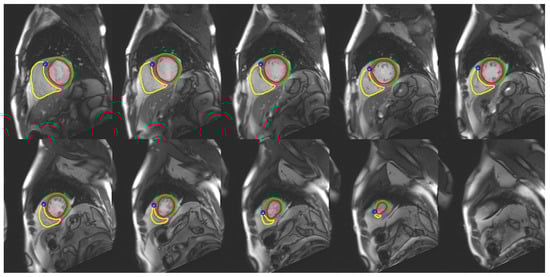

3.2. Image Segmentation